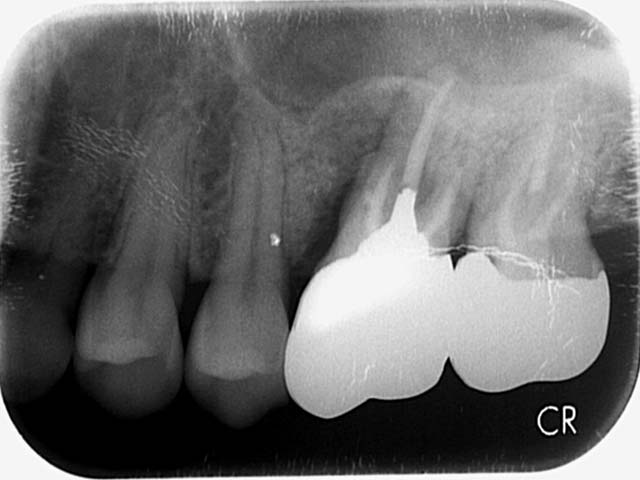

微創植牙 首頁 案例分享 人工植牙 微創植牙 微創植牙 牙周病的牙齒,因為骨頭破壞,只好拔除 拔牙後,置入骨粉,靜待骨頭癒合 晴美牙醫擁有豐富竹北微創植牙經驗,欲瞭解更多相關知識,可至診療項目-微創植牙頁面。 傷口癒合良好 微創不翻瓣 置入植牙 裝置假牙